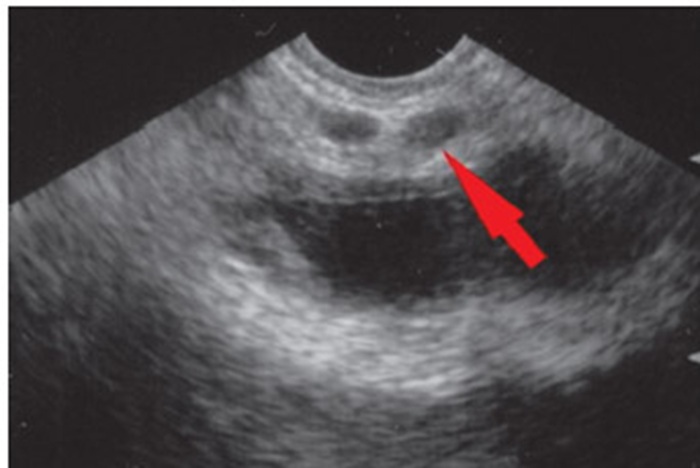

На первом этапе происходит изучение почек, мочевого пузыря, мочеточников и других элементом мочевыделительной системы. Процедура позволяет оценить их размеры, форму, структуру. Также выявляют камни, полипы или другие патологии.